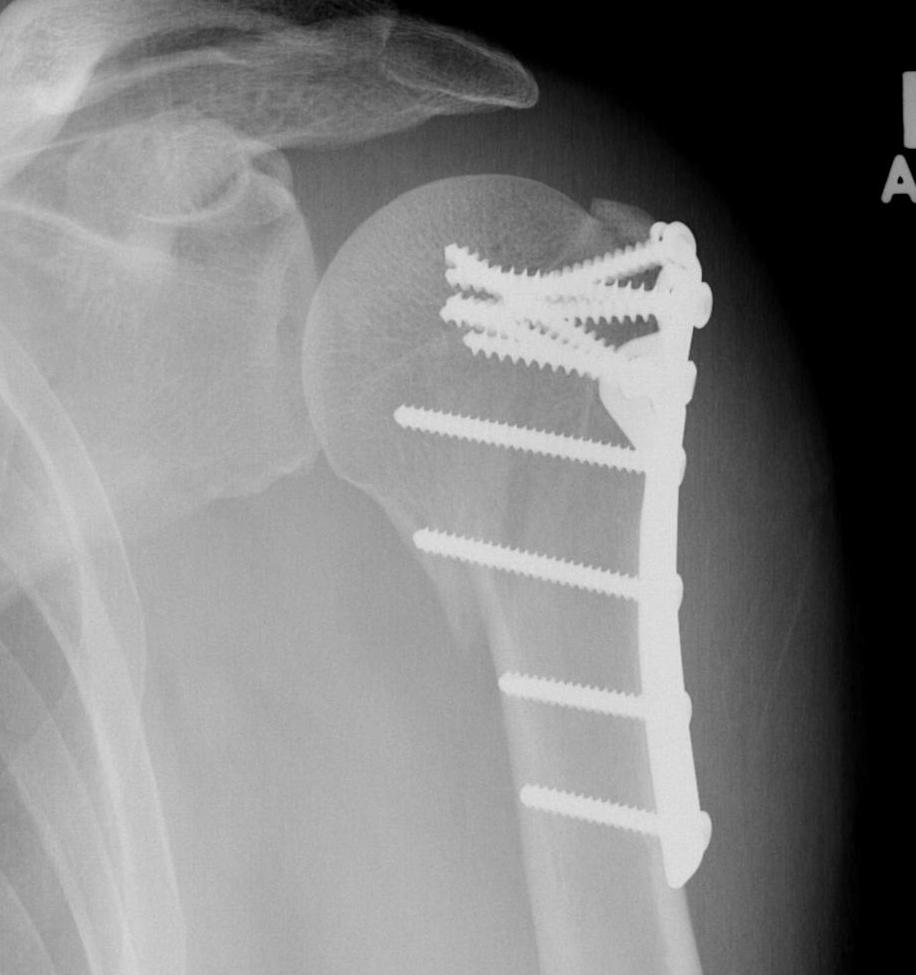

proximal humerus fracture Background ORIF with locking plate Arthroplasty Greater tuberosity fractures Lesser tuberosity fractures / avulsions Book traversal links for Proximal humerus fractures ‹ Pectoralis Major Tears Up Background ›